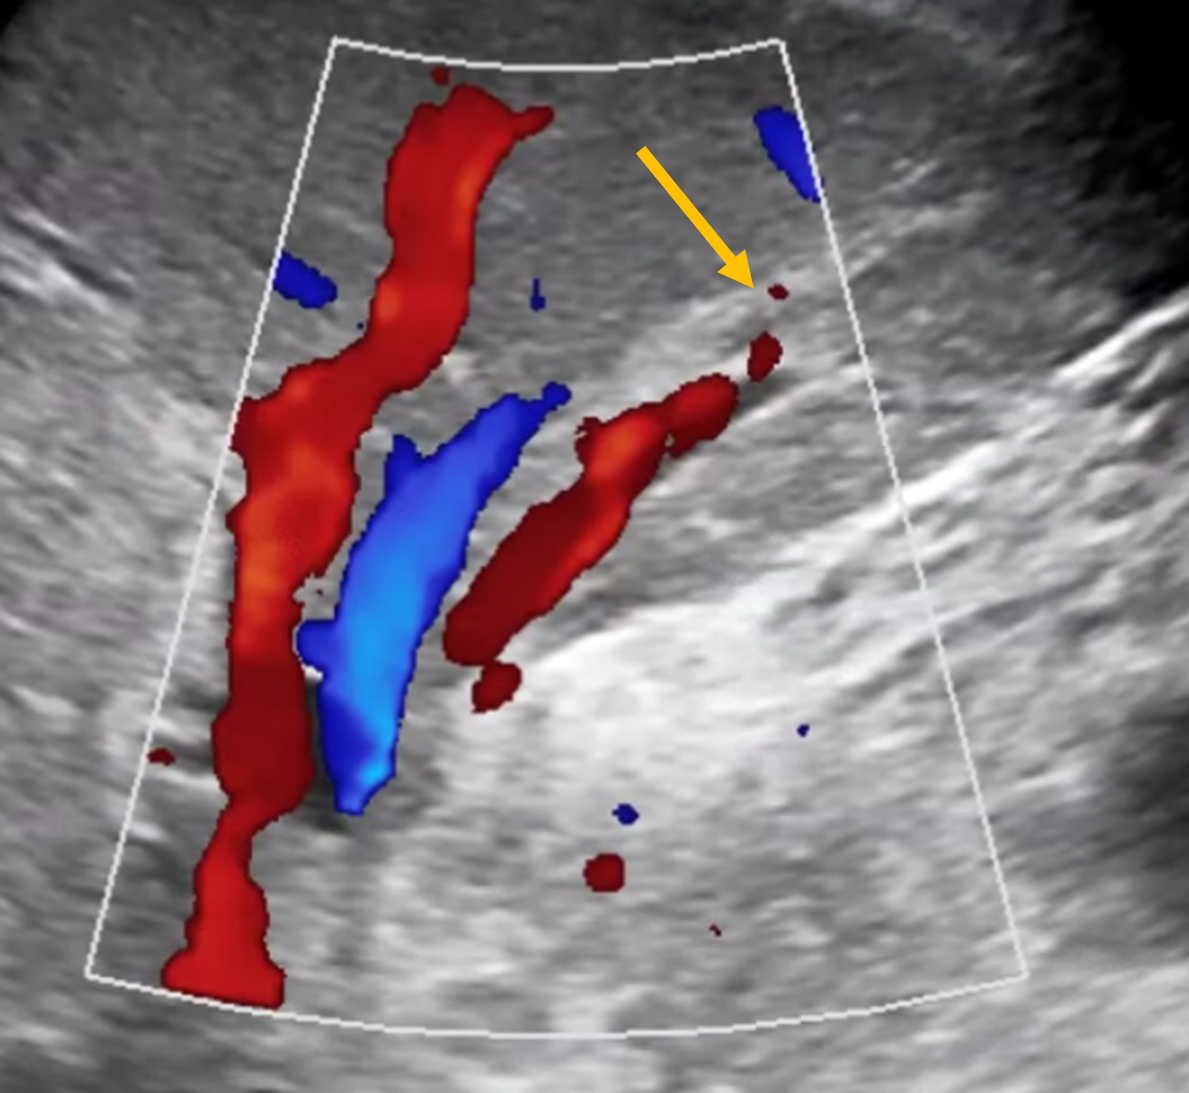

초음파로 늘어난 간내담관을 확인합니다.

위에 제가 올린 CT 처럼 간내담관이 아주 늘어난 경우에는 초음파로도 담관이 잘 보입니다.

초음파로도 잘 보이는 경우에는 초음파를 보고 바늘로 담관을 찌릅니다.

하지만? 만약 초음파에가 간내담관이 잘 보이지 않는다면

해부학적 지식을 이용해서 엑스레이 장비를 이용해서 간내담관 천자를 시도합니다. (경우에 따라선 매우 여러번 찌를 수도 있습니다. 정말 어쩔 수 없는 부분입니다.)